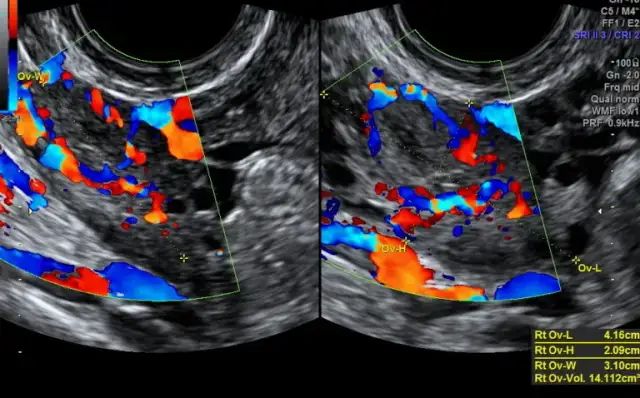

Andrologowie przeprowadzają szereg badań diagnostycznych, które są niezbędne do oceny stanu zdrowia mężczyzn. Do najczęściej wykonywanych badań należy analiza nasienia, która pozwala ocenić jakość i ilość plemników. Inne istotne badania to testy hormonalne, które pomagają w diagnozowaniu zaburzeń hormonalnych, oraz badania obrazowe, takie jak ultrasonografia, które umożliwiają ocenę narządów płciowych. Te badania są kluczowe dla ustalenia przyczyn problemów zdrowotnych i zaplanowania odpowiedniego leczenia.

| Ultrasonografia | Ocena narządów płciowych |